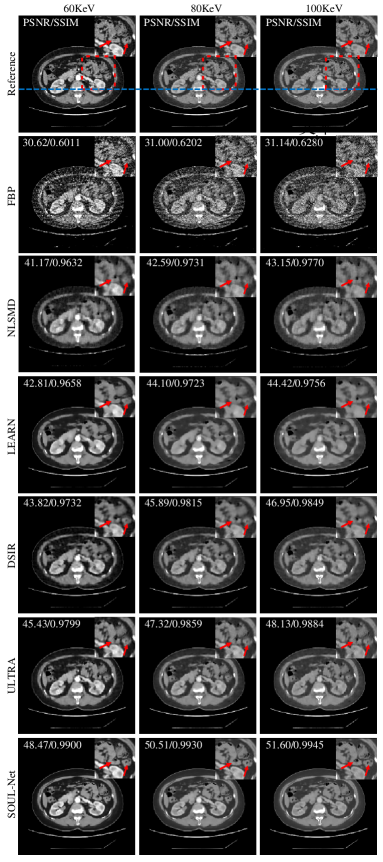

Figure 2: Reconstruction results of different methods with simulated noisy abdominal data. Display window is [-160,240]HU.

Fig. 2 shows one representative abdominal slice reconstructed with simulated noisy data using different methods. Three typical energy bins (60 keV, 80 keV and 100 keV) are displayed. It can be seen that some details in the NLSMD result are blurred, although most noise and artifacts are suppressed. Similarly, some important structural details are smoothed by LEARN, DSIR and ULTRA. To better visualize the performance of detail recovery, the ROI indicated with red boxes in Fig. 2 are magnified. It can be observed that compared with other methods, SOUL-Net not only eliminates the noise and artifacts effectively but also maintains the structures effectively, especially in the parts indicated by red arrows. The SSIM and PSNR values of each reconstruction are shown in the upper left part of each subfigure in Fig. 2. Our method achieves the highest SSIM and PSNR values.

To better verify the detail recovery ability, Fig. 3 shows the absolute difference images associated with the reference image. In Fig. 3, it is clear that SOUL-Net has the smallest residual compared with other methods. This indicates that our method is able to preserve the structural details effectively.